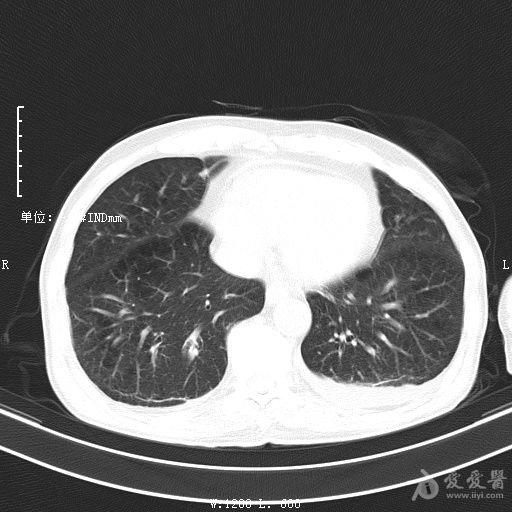

最新的肺炎疫情形勢嚴峻,病毒變異使得防控工作更加復雜,許多地方出現(xiàn)了新的病例,甚至有些地區(qū)的疫情出現(xiàn)了反彈,這不僅是對醫(yī)療系統(tǒng)的考驗,更是對每一個生命的考驗,我們需要密切關(guān)注疫情動態(tài),共同應對這場挑戰(zhàn)。??